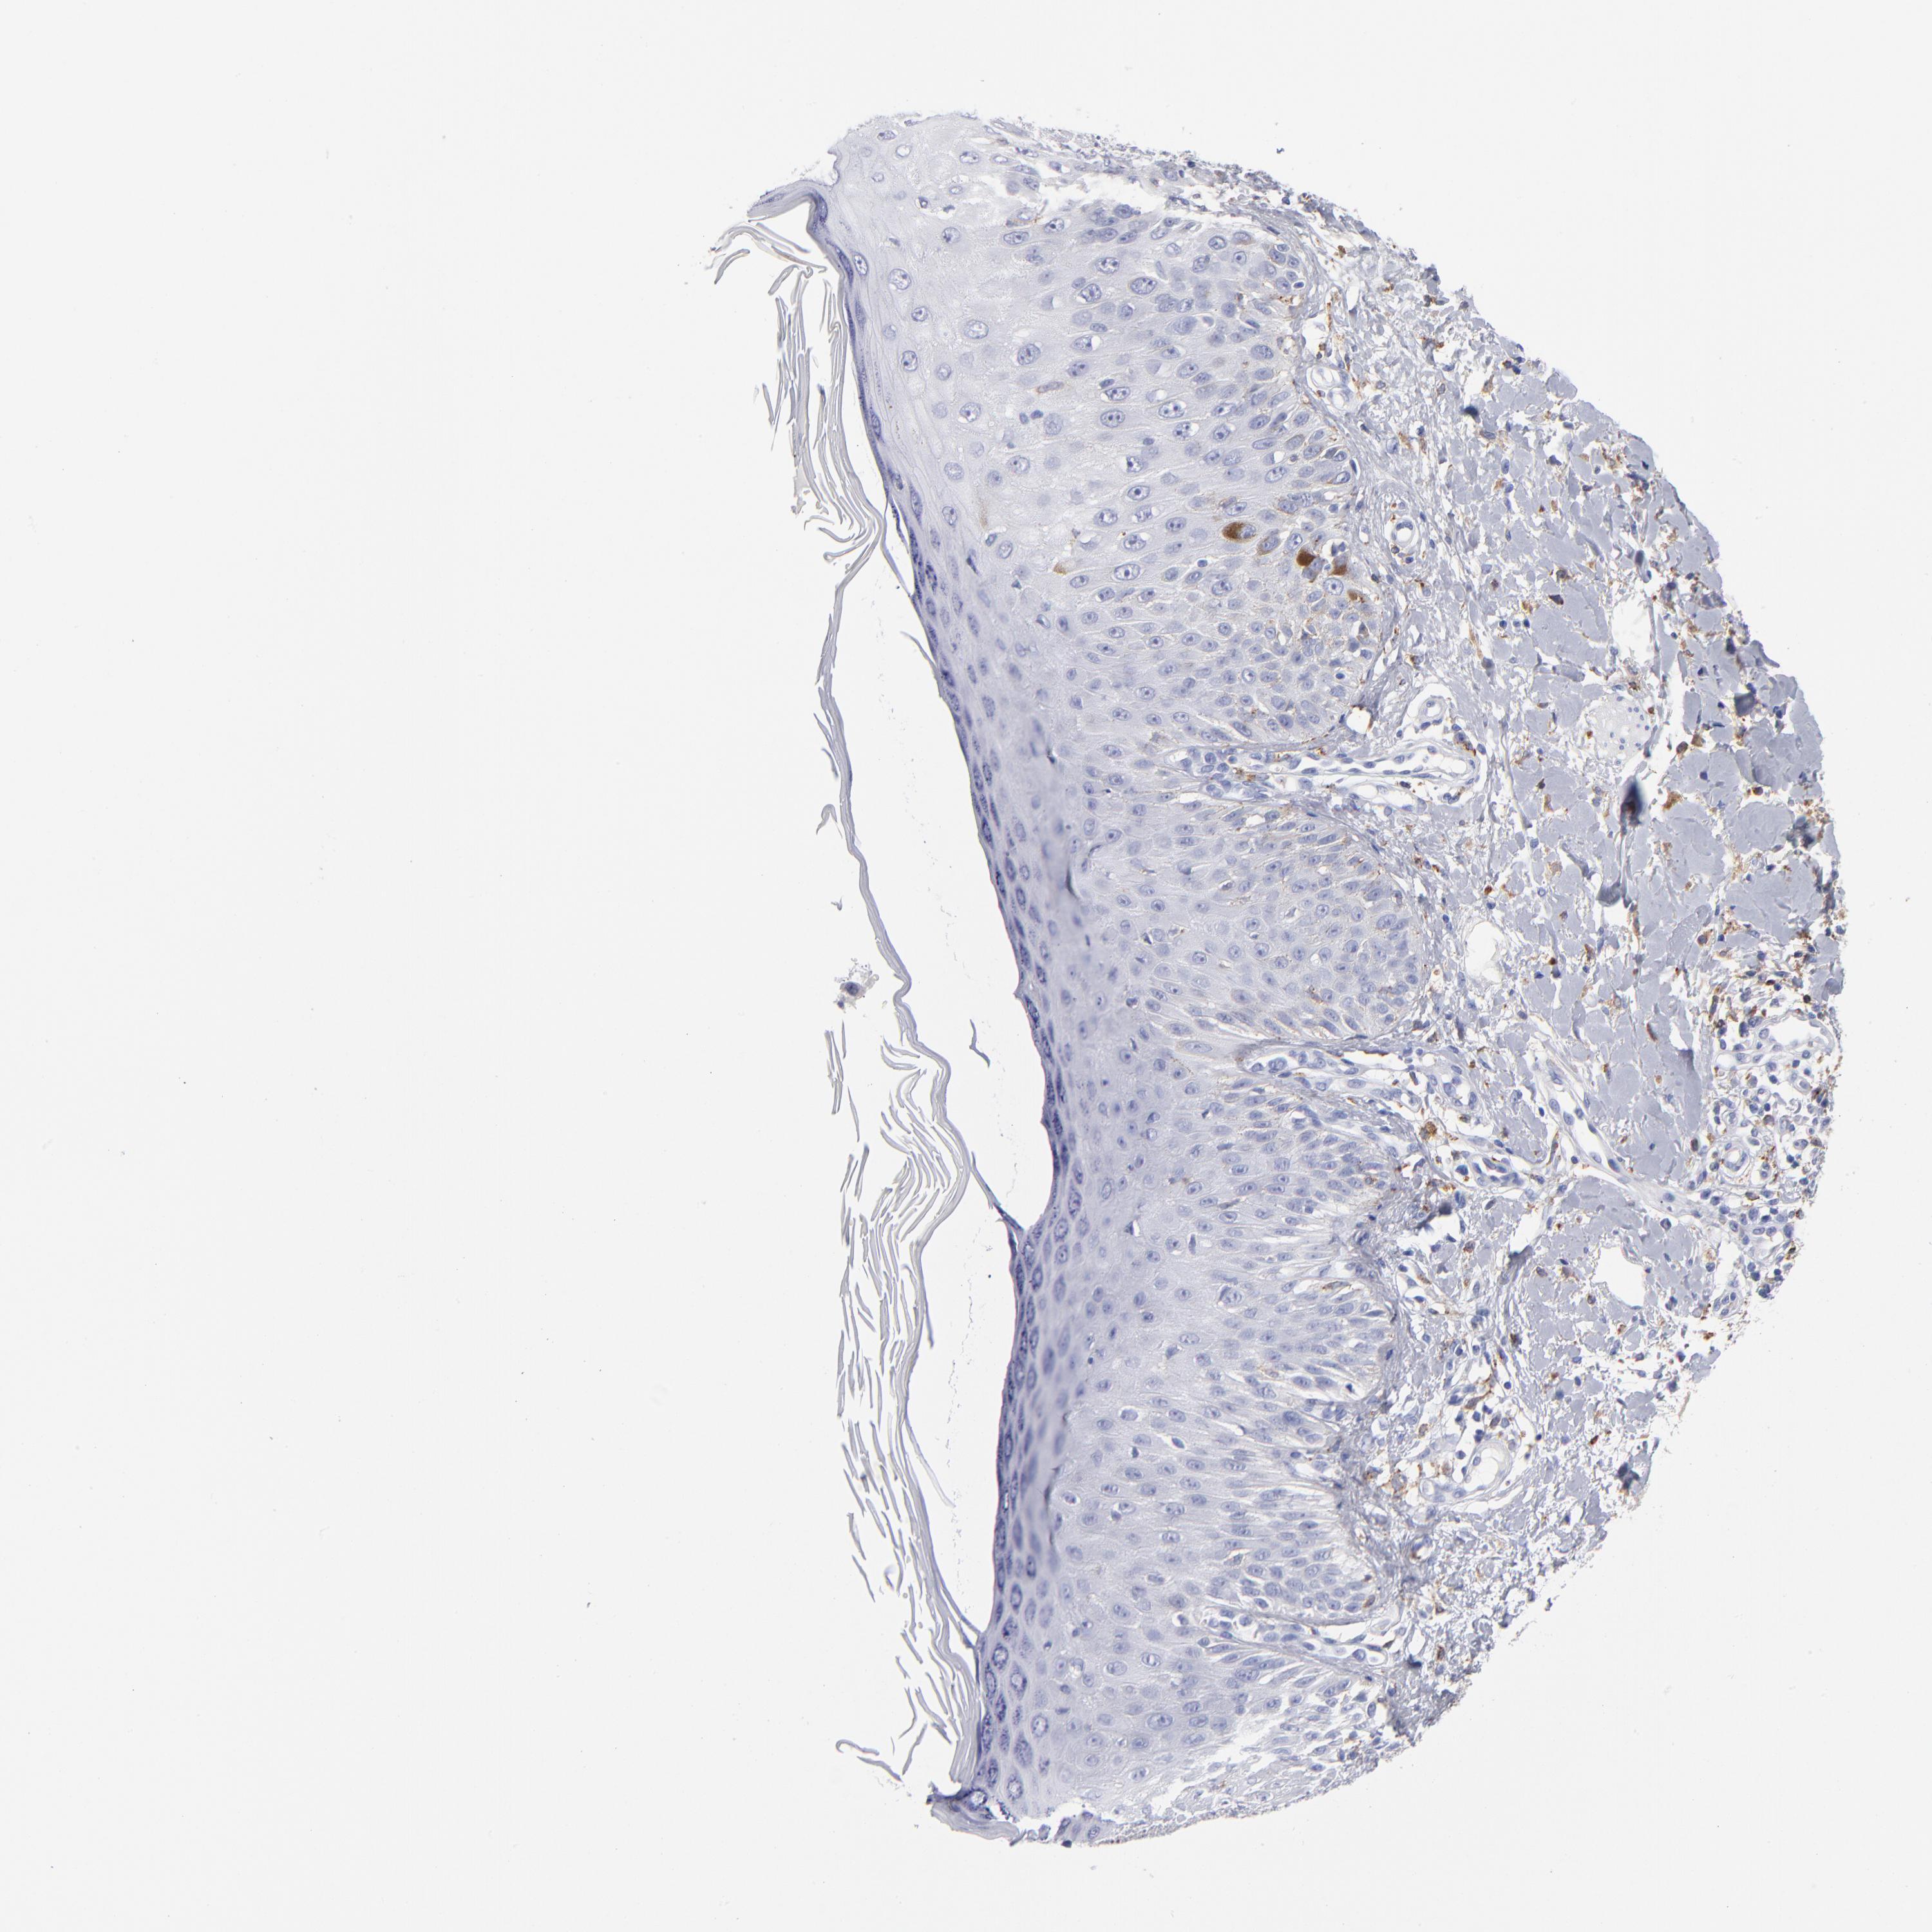

SKIN CANCER - Protein expressioni

A mouse-over function shows sample information and annotation data. Click on an image to view it in a full screen mode. Samples can be filtered based on level of antibody staining by selecting one or several of the following categories: high, medium, low and not detected. The assay and annotation is described here.

Antibody stainingi

Antibody staining in the annotated cell types in the current human tissue is reported as not detected, low, medium, or high, based on conventional immunohistochemistry profiling in selected tissues. This score is based on the combination of the staining intensity and fraction of stained cells.

Each image is clickable and will lead to virtual microscopy that enables deeper exploration of all samples and also displays staining intensity scores, fraction scores and subcellular localization as well as patient and tissue information for each sample.

Antibody HPA003740

Squamous cell carcinoma, NOS

Basal cell carcinoma